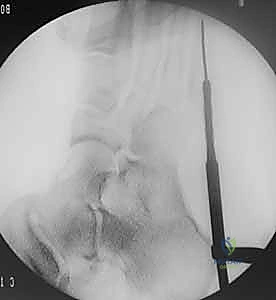

- يتم تجهيز غرفة العمليات بأحدث أجهزة التصوير الإشعاعي الفوري (C-arm) لضمان الدقة المطلقة.

- إدخال سلك التوجيه (Guide Wire): تحت توجيه الأشعة السينية المباشرة في غرفة العمليات، يتم إدخال سلك معدني رفيع جداً ليمر عبر الكسر وصولاً إلى النخاع العظمي. هذه الخطوة تتطلب دقة متناهية لضمان أن السلك في المنتصف تماماً.

- التحضير والتوسيع (Drilling/Tapping): يتم استخدام مثقاب خاص مجوف يمر فوق سلك التوجيه لتوسيع القناة النخاعية وتجهيزها لاستقبال المسمار.

- إدخال المسمار التيتانيوم (Screw Insertion): يتم اختيار مسمار طبي من التيتانيوم (طوله وسمكه محسوبان بدقة لتناسب عظمة المريض). يتم إدخال المسمار ليربط بين جزئي الكسر، مما يولد قوة ضغط (Compression) تجعل حواف العظم متلاصقة تماماً، وهو السر وراء الالتئام السريع.